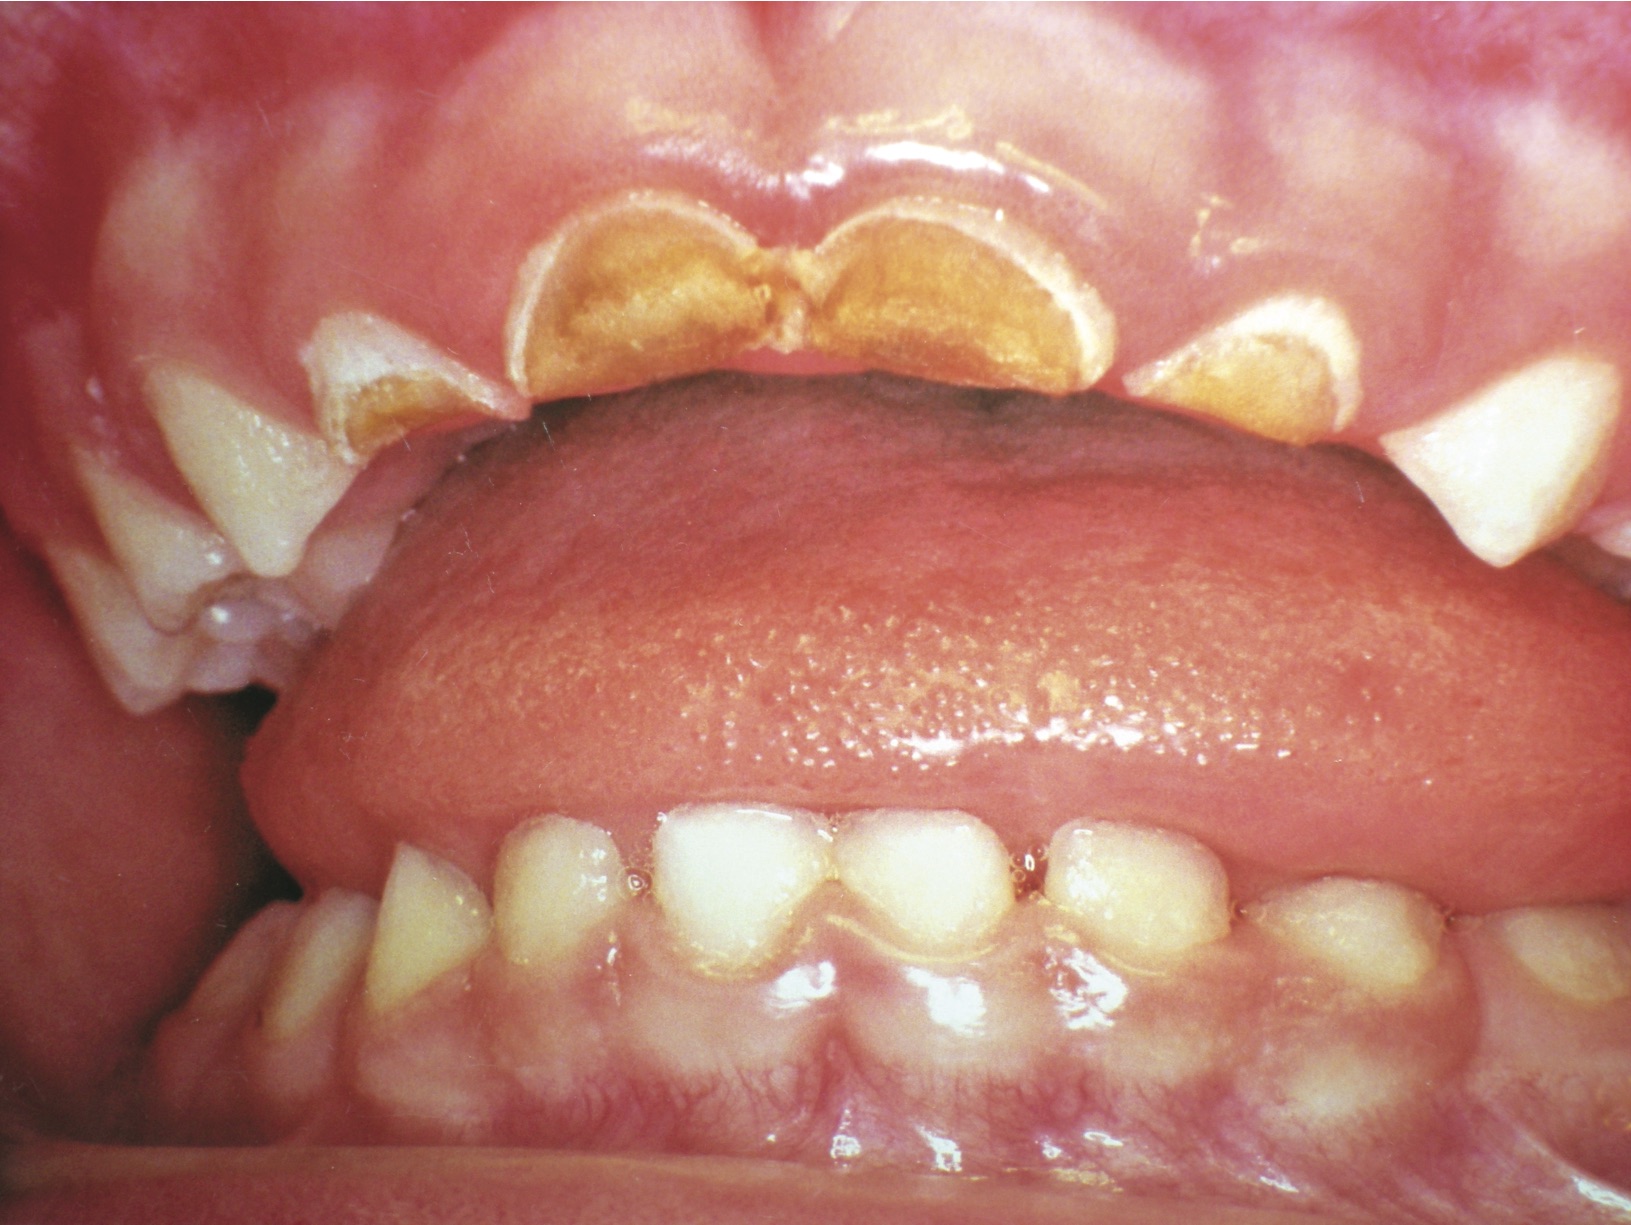

This presentation is classic Early Childhood Caries (ECC), when 6 or more of 20 teeth are decayed (Figure 4). If any abscesses are present, the author recommends 1 week of antibiotics and removal of the tooth.21 When a child’s first dental visit is associated with pain and a potentially uncomfortable procedure, many future “happy visits” will be required to rebuild rapport and trust. After 1 week of antibiotics, it is usually possible to obtain adequate anesthesia for removal of a single tooth. Many practitioners report that local anesthetics are more effective when the acute phase of a bacterial infection has passed after administration of antibiotics. The use of a Molt mouth prop and caregiver assistance with gentle restraint helps guarantee control of the situation for the limited time necessary for removal of the tooth.

Figure 4  Classic early childhood caries demonstrating massive destruction of maxillary anterior teeth.

Figure 4